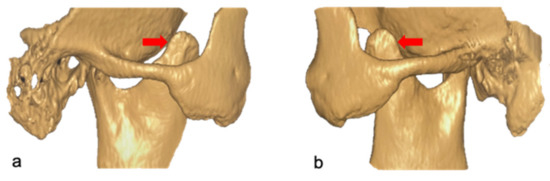

Mandibular Coronoid Process Hypertrophy: Diagnosis and 20-Year Follow-Up with CBCT, MRI and EMG Evaluations

2. Clinical Case